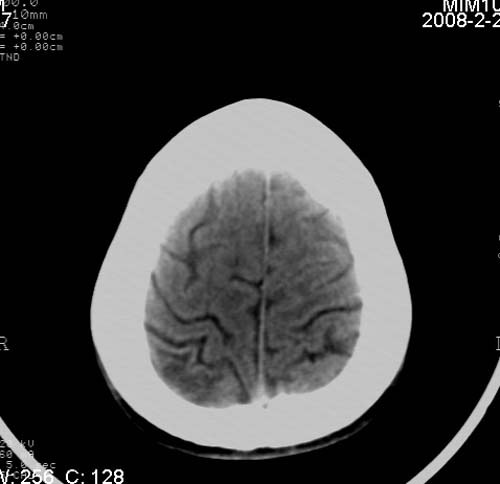

男,17岁,3天前与人斗殴,自述头痛、头晕。无恶心、呕吐,无阳性体征,一般情况良好。

病灶以钙化为主,无明显占位效应,病灶周围无水肿,这种情况应该是脑血管畸形,最多见的是动静脉畸形,其次是海绵状血管瘤.

病人较年轻,有头疼、头晕症状,动静脉畸形可能性大。